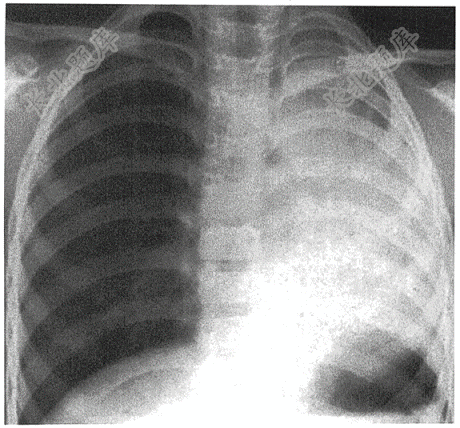

- 单项选择题女性,65岁。胸闷左侧呼吸音低一周( )

A、左侧胸腔积液

B、左全肺不张

C、左侧肺炎

D、左肺肺癌

E、左侧水肿